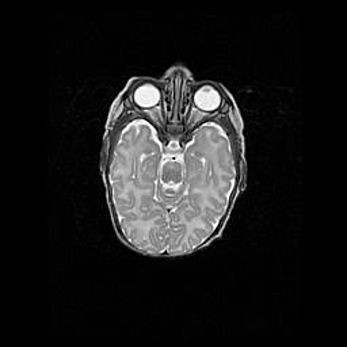

Лейкомаляция с кистозно-глиозной дегенерацией головного мозга.

Возраст: 2 месяца 25 дней

Вес: 6400 г

Окружность головы: 40 см

Срок гестации: 41 неделя

Лейкомаляцию относят к ишемически-гипоксическим повреждениям головного мозга, диагностируемым у новорожденных. При лейкомаляции в головном мозге обнаруживают очаги некроза, возникшие после тяжелой гипоксии и нарушения кровотока. В процессе морфогенеза очаги проходят три стадии: 1) развития некроза, 2) резорбции и 3) формирования глиозного рубца или кисты. Перивентрикулярная лейкомаляция (ПЛ) встречается примерно в 12% случаев среди новорожденных, обычно – у недоношенных детей, причем, частота ее зависит от массы, с которой младенец появился на свет. Наибольшее число малышей страдает лейкомаляцией, если масса при рождении 1500-2500 г.